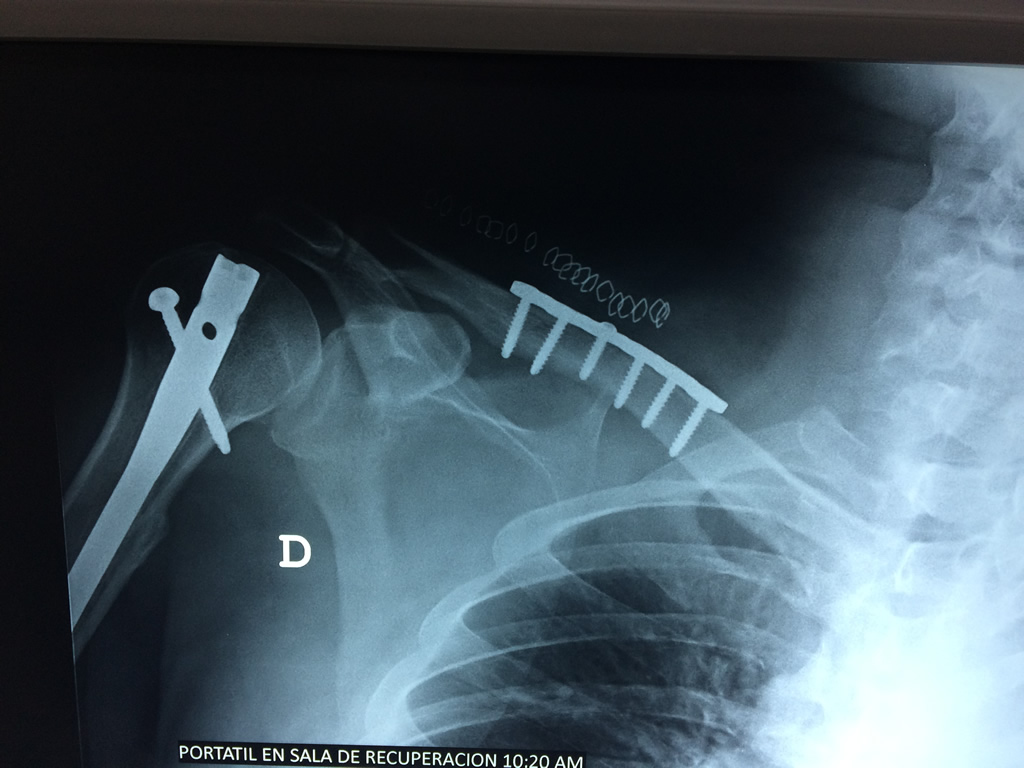

Cirugías de Calcaneo - Clavícula